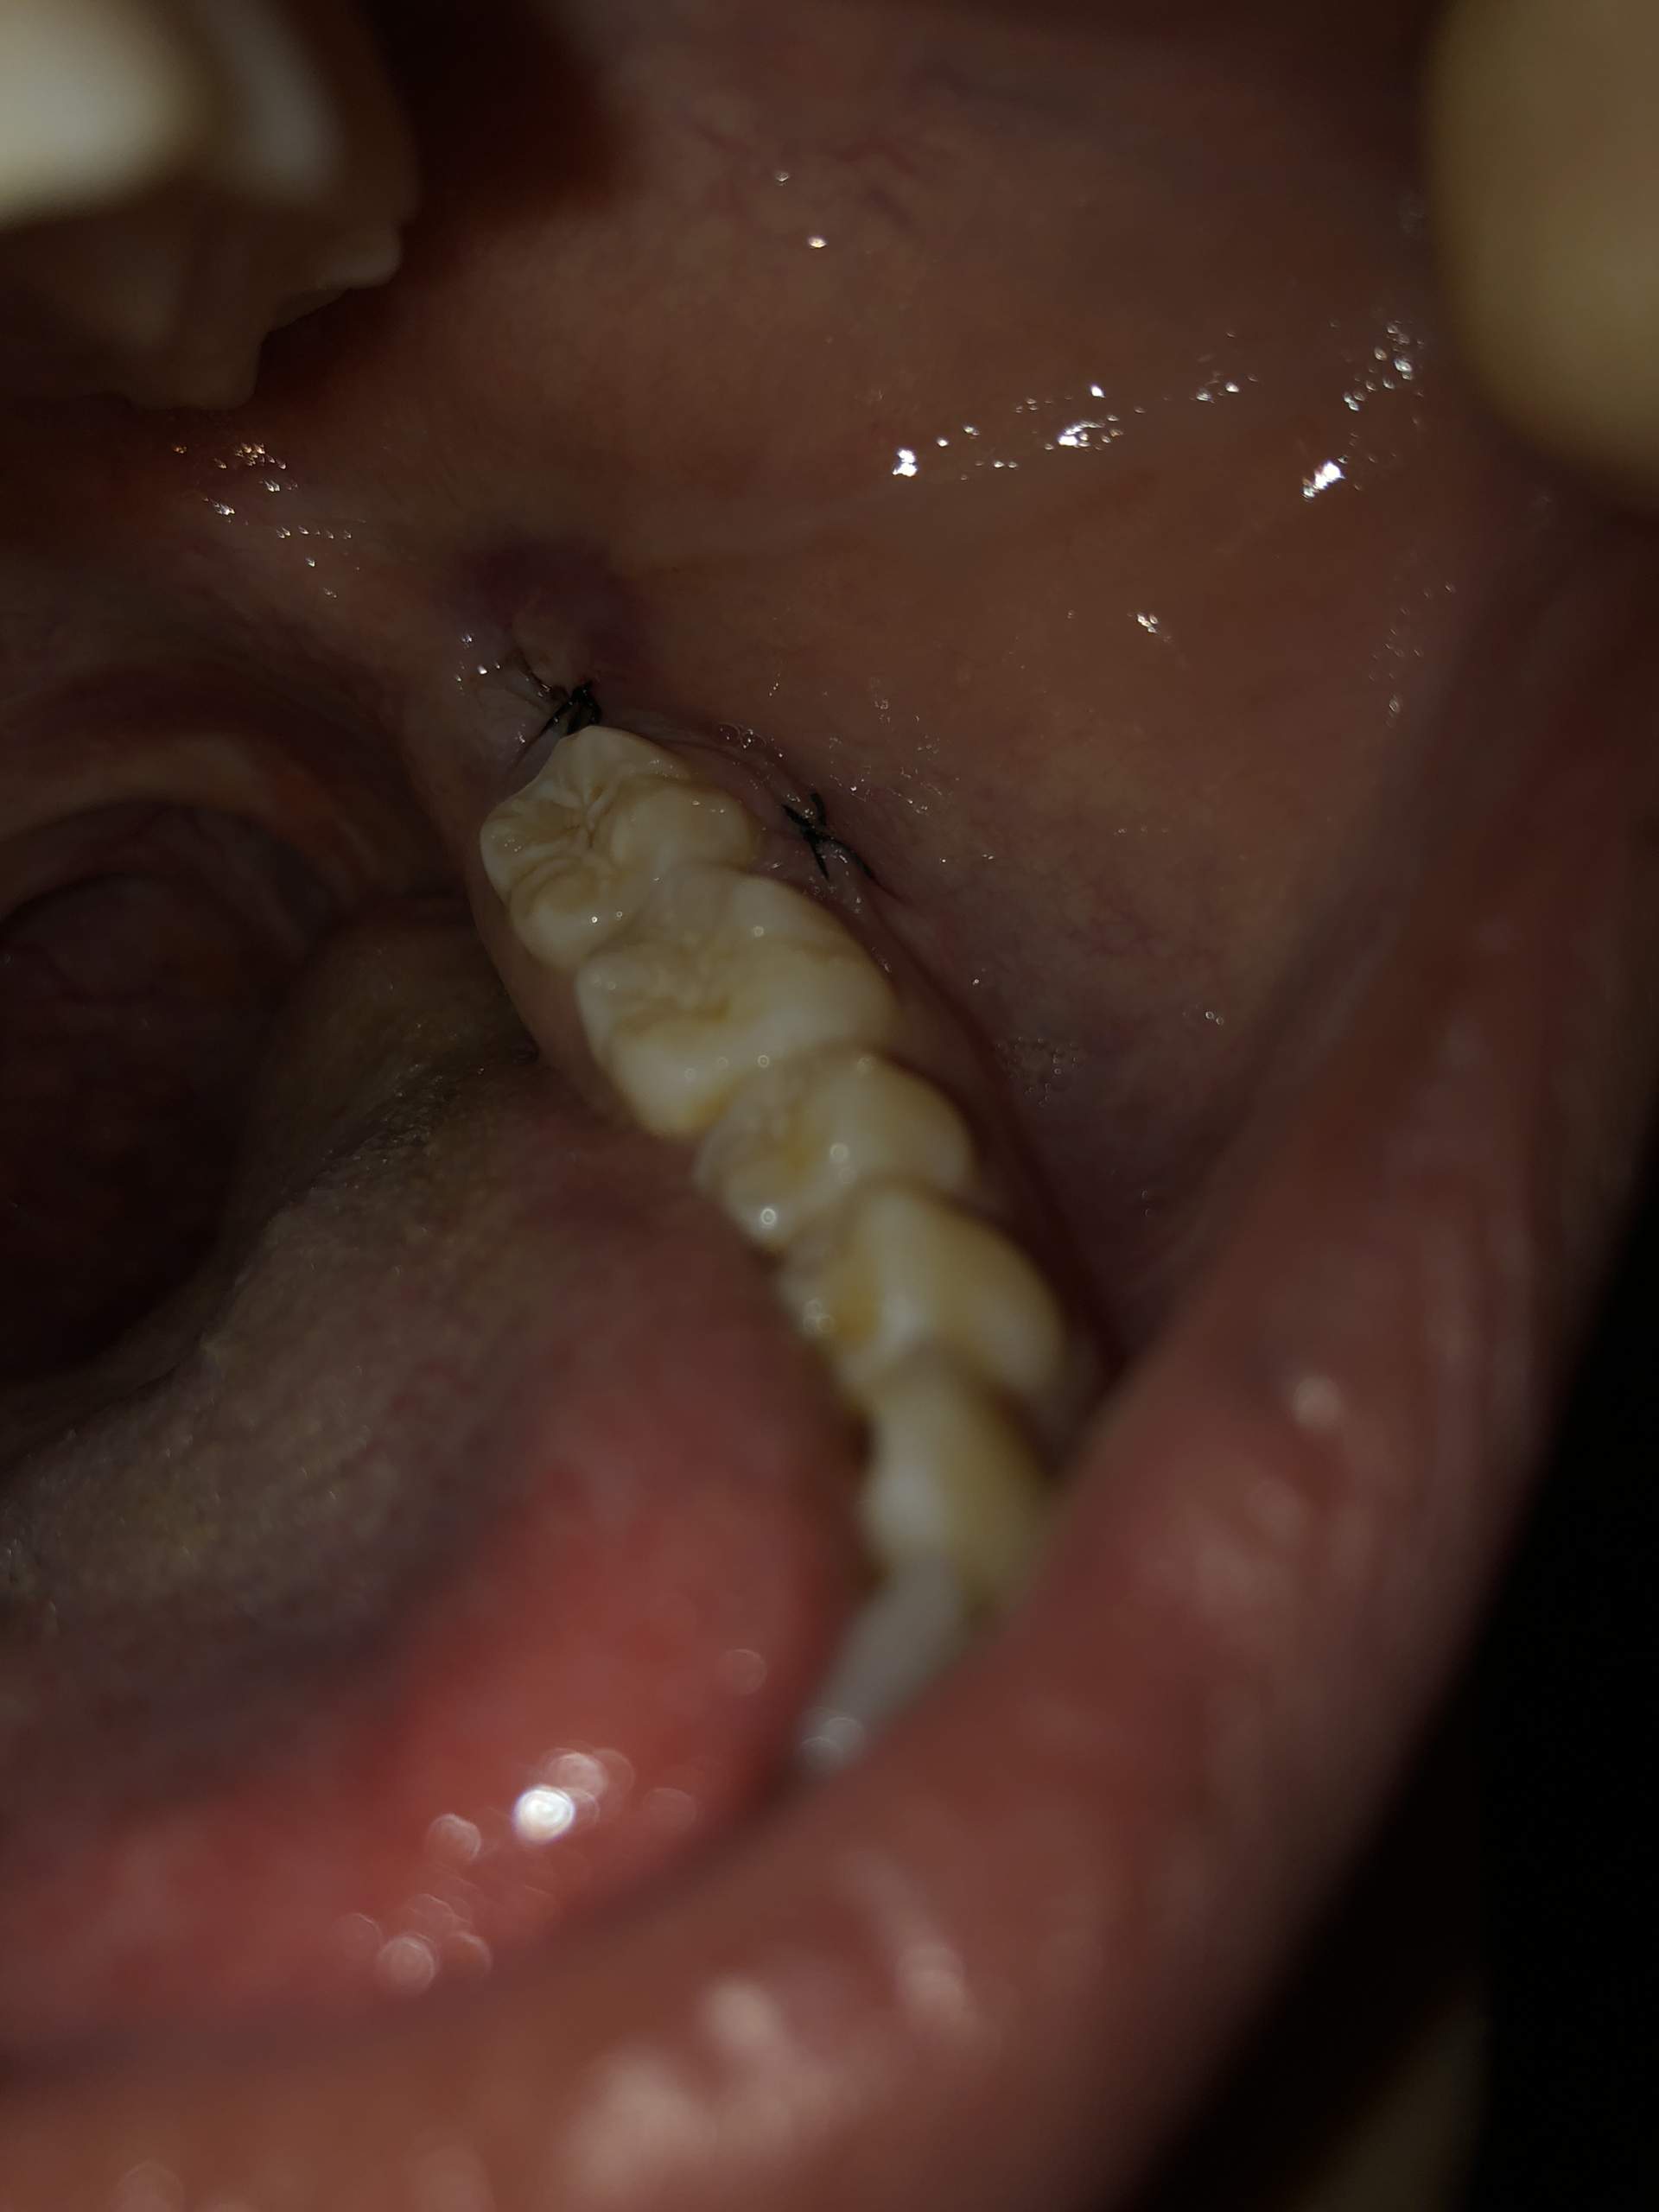

Weisheitszahn Heilung

Warum kann man den Mund nach der Weisheitszahn-OP nicht öffnen? Warum entsteht Mundgeruch . Du musst bei der Entfernung von Weisheitszähnen und Wurzelspitzenresektionen im Frontzahnbereich mit etwa 2-4 Tagen Arbeitsunfähigkeit rechnen. Erste-Hilfe-Tipps bei Weisheitszahn-Schmerzen. 1/3 Was sind Weisheitszähne? Extrahieren oder . In der Regel stellt der behandelnde Zahnarzt Dir dafür . Bei schwierigeren Weisheitszähnen und Wurzelspitzenresektionen im Seitenzahnbereich kann es schon . In den ersten 24 Stunden nach der Operation solltest du eine kalte Kompresse auf deine Wange legen, um die Schwellung und den Schmerz zu lindern.Hallo! Vielleicht bist du gerade dabei herauszufinden, wie lange nach einer Weisheitszahn-OP die Schwellung andauern kann. Die Schmerzen nach einer Zahn OP können . Danach kannst du so oft wie nötig kühlen, aber versuche, es nicht zu oft zu .Wundheilung Was nach einer Weisheitszahn-OP wichtig ist.Allgemein, Heilungsphase. Mit welcher Heilungsdauer ist nach der Weisheitszahn OP zu rechnen und wie verläuft die Heilung generell? Das sind Fragen, die sich viele Patienten .Ein Schlüsselbestandteil von Ananassaft ist das Enzym Bromelain. Aber auch wenn keine ernsthafte Wundheilungsstörung oder Erkrankung vorliegt, können Sie bei der Wundbehandlung viel tun, um die Heilung zu beschleunigen. mit einem Verband wechseln, die Wunde desinfizieren und die Heilung fachmännisch beobachten. Weisheitszahn-OP: 3-7 Tage Ruhe gönnen für besten . Nach der Weisheitszahnentfernung sollte man seinem Körper Ruhe und .

Die Fäden werden normalerweise nach 7 bis 10 Tagen entfernt. Du kannst nach einer Weisheitszahn-OP in der Regel nach 24 Stunden wieder Schokolade essen.2022 06:00 Uhr. Ob nach einem Schnitt mit dem Küchenmesser . 30 Minuten auf ein Tuch oder auf eine Kompresse zu beißen.Lebensmittel, die die Wundheilung im Mund fördern. Wenn du Schmerzen oder Schwellungen nach der Operation hast, solltest du deinen Zahnarzt kontaktieren und dich erkundigen, was du tun kannst, um es zu lindern.Wir empfehlen dir, die Kompressen mindestens die ersten zwei bis drei Tage nach der Verletzung anzuwenden.Weisheitszähne: Schmerzen, Symptome und Ablauf der OP. Dabei gibt es in der Regel keine .Nach einer Weisheitszahn-OP sollte man mindestens 48 Stunden warten, bevor man wieder Kaffee trinkt, um die Heilung nicht zu beeinträchtigen.